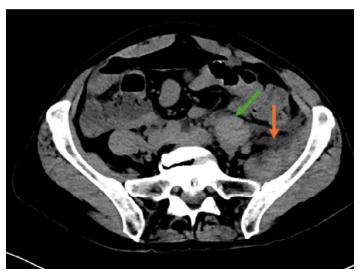

Case report: We present the case of a 64-year-old female with a history of hypertension, hyperlipidemia, and breast cancer who developed acute kidney injury (AKI) and retroperitoneal necrotizing fasciitis following a 20-mile bike ride. The patient's initial symptoms included severe muscle aches, nausea, vomiting, and flank pain. Diagnostic imaging and laboratory results indicated myositis and severe AKI. Despite aggressive treatment with antibiotics, intravenous fluids, and pain management, the patient developed septic shock and multiorgan failure, ultimately leading to her death.